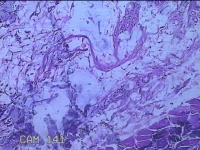

右手掌肿物

性别

女

年龄

32岁

临床诊断

1.右手掌肿物性质待查?右腕管综合征

一般病史

发现右手掌肿物疼痛伴拇示中指感觉迟钝约6年。

标本名称

大体所见

灰白粉红色肿物2.5x2x0.8cm一个,表面光滑,切开肿物呈实性,切面灰白粉红色,质软。